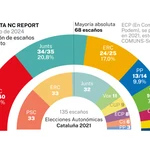

Un avance del Instituto de Investigación Biomédica de Barcelona llena un vacío fundamental de conocimiento sobre la formación del aparato principal de la división celular, el huso mitótico. La visualización y seguimiento en vivo de los extremos iniciales de los microtúbulos, filamentos que organizan el huso mitótico, ofrece una imagen más comprensible de su arquitectura dinámica. Sus resultados también ayudarán a entender cómo actúan fármacos usados en quimioterapia cuyo blanco son los microtúbulos.

"Miles de ellos", explica el biólogo celular del Instituto de Investigación Biomédica (IRB Barcelona), Jens Lüders, "filamentos finos, imprescindibles y extremadamente dinámicos y cambiantes, a los que al fin, hemos podido marcar en su extremo inicial y seguir su localización y movimiento durante el ensamblaje y arquitectura del huso mitótico". El avance lo publica la revista Nature Cell Biology.

"Durante más de 10 años solo hemos podido rastrear los finales de los microtúbulos pero no había nada para los inicios lo que suponía un cuello de botella para la investigación del huso mitótico y para entender mejor su función en la división celular", describe Lüders. El científico alemán es el jefe del grupo Organización Microtubular en el IRB Barcelona, y ha tutelado el estudio que lleva únicamente dos nombres, el suyo y el del francés Nicolas Lecland, primer autor, quien ha desarrollado su doctorado con una beca de "la Caixa"en el IRB.

Los científicos han conseguido demostrar que la proteína gamma tubulina (g-tubulin) se localiza en los inicios de los filamentos microtubulares y se mantiene relativamente estable asociado a estos. Después han preparado un marcador fluorescente que se adhiere a γ-tubulin y que activan mediante foto activación por láser para filmar en vivo la evolución de los extremos iniciales de los microtúbulos en el huso mitótico de células humanas en división.

En la puesta a punto de la tecnología ha sido clave la Plataforma de Microscopía Digital Avanzada compartida por el IRB Barcelona y el Parque Científico de Barcelona, y que está dirigida por el físico francés del IRB, Julien Colombelli.

Los investigadores describen por primera vez dónde se generan dentro del huso la mayor parte de los microtúbulos, cómo evolucionan y cómo se transportan mediante la acción de tres proteínas motor, hacia los polos opuestos de la célula, donde se anclan.

Simultáneamente a este proceso, los extremos opuestos de los filamentos se alargan hacia el centro de la célula donde interactúan con los cromosomas. Cuando el huso esté finalmente dispuesto, los microtúbulos tirarán de los cromosomas para iniciar la división.